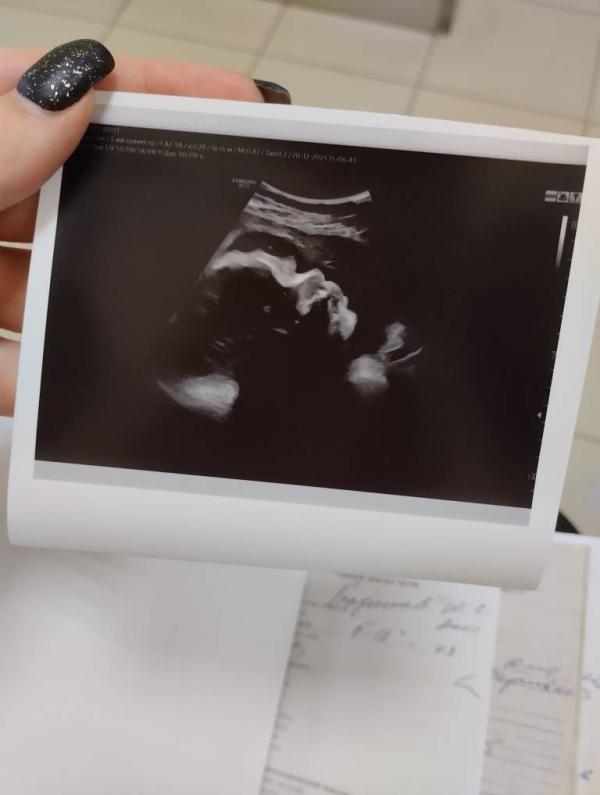

Ждём 💙